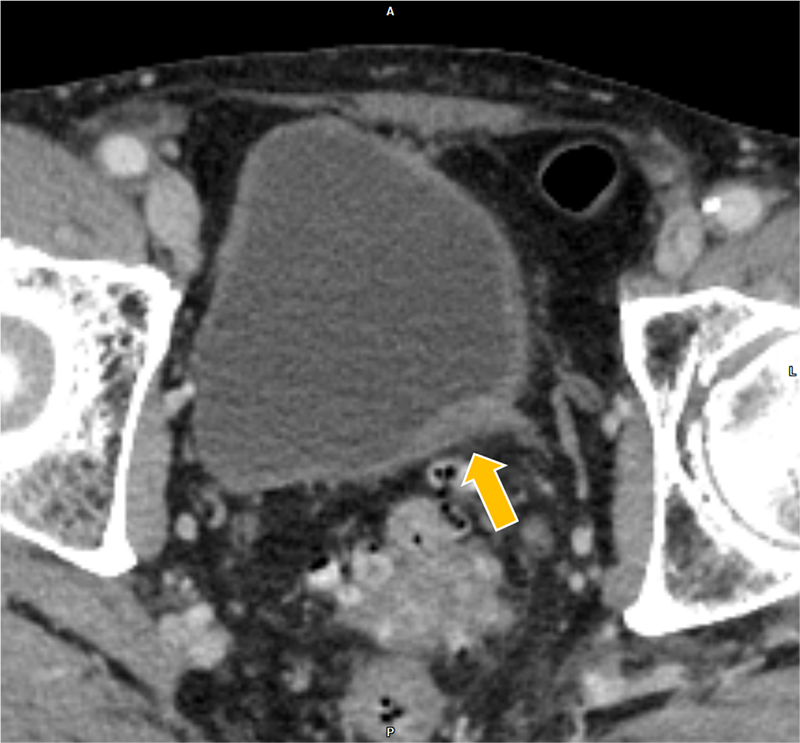

膀胱癌の治療経過観察中、胆嚢癌が疑われ、術前精査目的に肝ダイナミックCTが施行された。胆嚢底部に長径30mm程の腫瘤を認めた。また、胆嚢左側や背側にリンパ節転移を疑う造影結節を認めた。さらに、同CTで前立腺左葉から直腸左側にかけての膿瘍形成が指摘され、後の精査でBCG注入療法に伴う骨盤内BCG感染症が明らかとなった。膿瘍の治療過程で腹膜播種が出現、胆嚢癌は化学療法の方針となった。